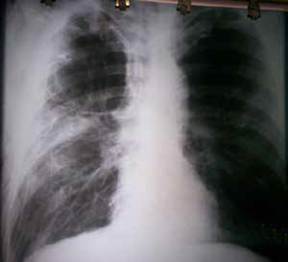

En la radiografía postero-anterior inicial de tórax en bipedestación se encontró colapso del pulmón derecho con múltiples bullas enfisematosas en ambos campos pulmonares (figura 1). El lóbulo superior derecho presentaba signos de atrapamiento de aire por la existencia de enfisema pulmonar, con aumento de su radiotransparencia. Las costillas se encontraban ‘horizontalizadas’ y había ensanchamiento de los espacios intercostales, y descenso y aplanamiento del diafragma.

Figura 1. Radiografía de tórax, postero-anterior y en bi-pedestación, en la que se observa el colapso del pulmón derecho con múltiples bullas enfisematosas en ambos campos pulmonares.